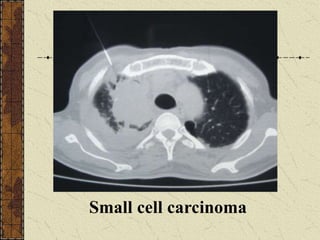

Small cell carcinoma